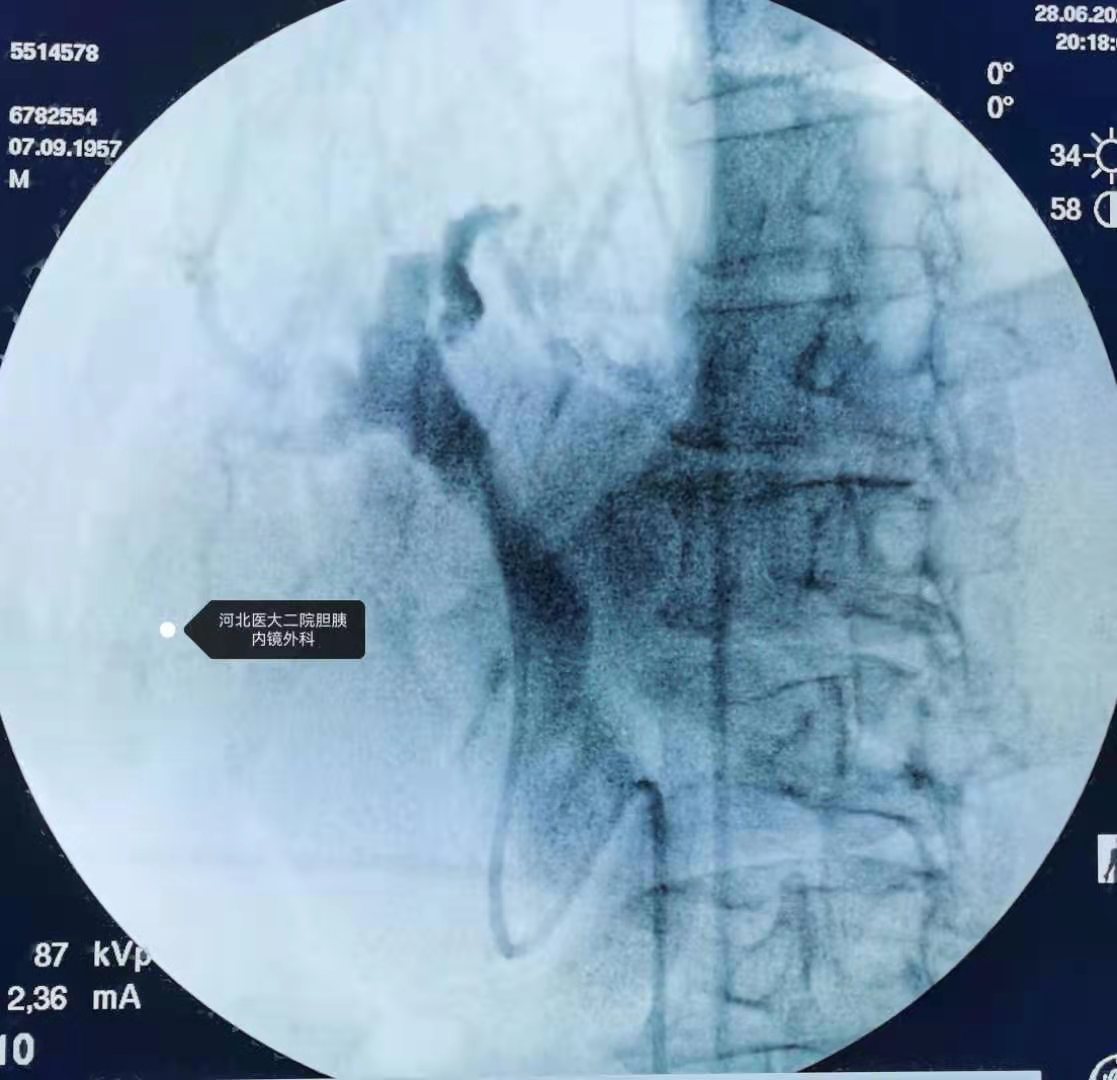

换用胃镜+透明帽行ERCP,找到输入攀及乳头开口

扩张

取石

鼻胆管